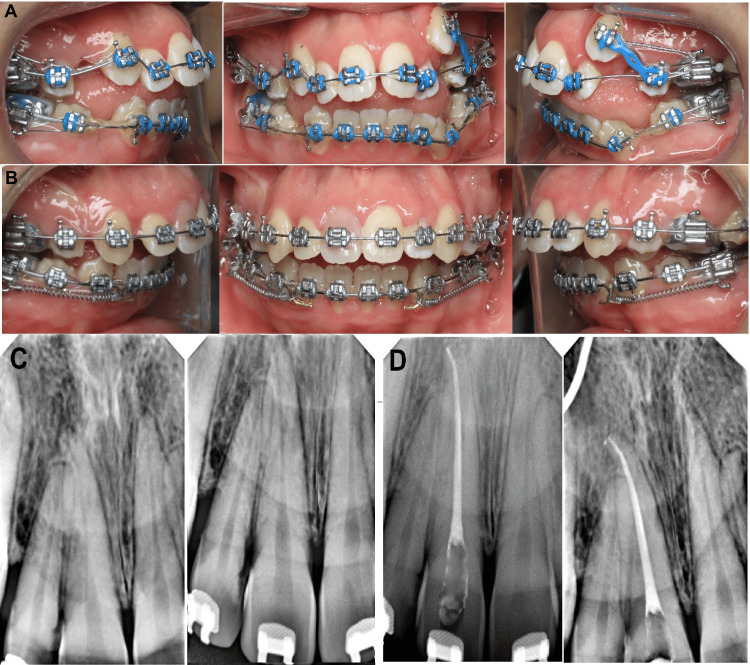

Treatment was started by bonding the fixed orthodontic appliances for both maxillary and mandibular teeth using 0.022×0.028 inch slot straight wire appliances with McLaughlin-Bennett-Trevisi (MBT) prescription (Gemini; Monrovia, CA: 3M Unitek). For anchorage, the transpalatal arch (TPA) was used with molar bands. A 0.014-inch nickel-titanium (NiTi) archwire was engaged through the brackets except for the maxillary left canine (23) because it was displaced high labially. After two months, a 0.016-inch (NiTi) archwire was inserted to continue the alignment of the teeth. An intraoral photograph taken after four months of bonding the braces showed tooth number 11 with normal color (Figure 3A). After that, a 0.017×0.025 inch (NiTi) archwire was inserted in the bracket slot to continue the alignment. When the teeth were aligned, a 0.016×0.022 inch stainless steel (SS) archwire was applied as a base archwire to preserve the maxillary arch form, whereas a 0.012-inch nickel-titanium (NiTi) archwire was inserted through the brackets of the displaced canine (23) by the piggyback technique. When tooth (23) reached the occlusion, a 0.016-inch (NiTi) archwire was engaged to align tooth (23) in the arch. Following receiving therapy for 10 months, an intraoral examination indicated that the maxillary right central incisor's labial and palatal surfaces of the crown were discolored (Figure 3B). The tooth had no caries, periodontal pockets, or restorations. The tooth displayed a slight degree of mobility. Electric pulp tests (Vitality Scanner; Glendora, CA: Analytic Technology) and cold testing revealed no abnormalities in any of the maxillary incisors (Endo-ice; Akron, OH: The Hygienic Corporation), except tooth #11. Radiographic examination revealed a radiolucent apical area for tooth #11 with widening periodontal ligaments of the tooth (Figure 3C). The root canal procedure for tooth 11 was scheduled after a necrotic pulp diagnosis. In order to apply clamps and rubber dams more easily, braces were taken off of the four maxillary incisors. The coronal access was accomplished using burs that covered the complete resorptive coronal defect; a working length was determined, and the intracanal tissue was removed while being heavily irrigated with a solution of 2.5% sodium hypochlorite. Debridement of the root canal was then performed, with a working length of 25.5 mm. The root canal was cleaned and shaped, then dried and completely filled with gutta-percha. The pulp chamber was restored using the CavitTM (Saint Paul, MN: 3M ESPE) during the same visit (Figure 3D).

Figure 3. Intraoral photograph during orthodontic treatment.

(A) After four months of treatment, (B) crown discoloration of maxillary right central incisors after eight months of treatment, (C) preoperative radiograph of the maxillary right central incisor revealing a periapical radiolucency with widening periodontal ligaments, and (D) postoperative radiograph after root canal treatment of maxillary right central incisor.